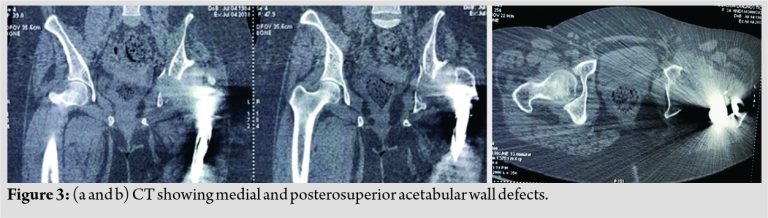

On the basis of CT of affected hip, which showed defects in medial and posterosuperior wall of true acetabulum (Fig. 3) a pre-operative 3D CT model of affected hip was printed to accurately assess the underlying acetabular defects and to see which acetabular reconstruction option worked best in current scenario (Fig. 4).

On the 3D model, a false acetabulum just superior to true acetabulum was noted; both acetabula being separated by a bony ridge. True acetabulum showed a breached medial wall, along with deficient posterosuperior wall and column defect. Pre-operative trialing was done using a Bursch Schneider cage of appropriate size on the 3D model of true acetabulum(Fig. 5). However, due to the presence of superior bony ridge between true and false acetabula, superior iliac flange of cage could not be seated over it properly. Hence, option of reconstruction of acetabular defect with tantalum posterior column wedge, tantalum cup, and tantalum augments was entertained.

Reconstruction of acetabular defect during Total Hip Replacement in Neglected DDH presents with unique challenges. In view of obscured surrounding landmarks, placement of acetabular cup in such cases is a difficult task. Some authors advocate placing the cup at high hip center, but studies have shown that elevation of hip center by even 1 mm, increases the load on hip to the tune of 0.1%, and increases body weight lever arm, leading to early failure of hip joint [1]. For cup to be stable and have adequate coverage at the level of true acetabulum, identification of true acetabulum and assessment of associated acetabular defects is required. Acetabular defects can be preoperatively assessed using 3D construction CT. In the present case pre-operative, 3D CT followed by 3D printing was used to print a model of pelvis with acetabular defects. This helped us to analyze configuration of true acetabulum and the associated defects. On 3D printing extent of posterosuperior and medial wall defect was identified. Along with a superior bony ridge could be seen separating the true from false acetabulum on 3D model. Although 3D CT reconstruction films have been used to preoperatively assess acetabular defects, 3D printed models are known to provide the surgeon with visual and tactile appreciation of acetabular defects preoperatively. Pre-operative templating and trialing of implants can be done on 3D models, thereby reducing chances of per-operative complications and reducing surgical time [4]. Studies have shown that 3D models help in pre-operative surgical simulation, enabling pre-operative cup, augment, buttress sizing, cage templating, thereby minimizing para-operative complications [5]. Reconstruction of posterosuperior defect is quite challenging with the literature coming up with various reconstruction options, such as autologous bone graft, allograft, cage along with autologous bone graft augmentation,Standard metal augments (prefabricated), and Custom made acetabular augments (3D printing). Each reconstruction option has its own merits and demerits. Some studies have advocated use of allograft or autograft for reconstruction of posterior superior acetabular defects. Although vascularized autografts hold the promise of better integration with iliac bone; donor site morbidity, graft failure, and graft resorption make autograft a less inviting option for reconstruction[6,7]. Graft resorption and failure may lead to secondary instability at hip[1]. Use of allografts is also limited because of complications such as graft failure and graft resorption. Second, bone bank facilities are not available in every institute, hence limiting the use of allografts for acetabular reconstruction[1].Some authors have used half and full cup cage constructs for major acetabular defects, but complications such as cup cage migration and non-progressive acetabular lucencies have been noted [8]. The use of trabecular metals is limited by their cost, but these have certain advantages. Potential advantage of trabecular metal is they have increased biocompatibility, allow bone ingrowth and fixation, hence a reasonable option in acetabular bone loss [9]. This helps to circumvent complications related with bone grafts and need of custom made implants or oblong cups [1]. In one of the studies acetabular defect was managed by trabecular acetabular cup, while associated anterior column defect was addressed by sliding iliac bone to construct acetabular column [10]. In the present case, initially, cage was planned for current acetabular defect, but it was found that superior bony ridge prevented sitting of iliac flange of cage on the acetabular margin. Hence, option of trabecular metal wedges and cup was exercised.